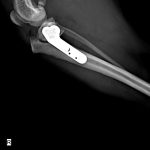

MIX犬(5.3kg)の右前十字靭帯断裂に対するTPLO術(脛骨高平部水平化骨切術)☑